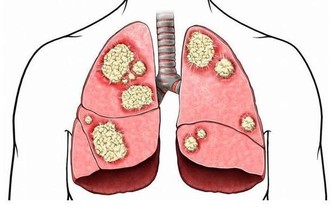

幾年前,一名44歲的法國男子因為時常覺得左腿無力,而前往醫院檢查,

沒想到一經診斷才發現,原來他的腦袋裡裝滿了液體,大腦竟然只剩下10%的面積。

後來進一步追蹤才發現,

原來這名男子小時候曾罹患腦水腫 (hydrocephalus,俗稱腦積水),

當時醫生以分流管排除他腦中的積水,一直到14歲時才停止。

但其實腦積水的問題未獲得根治,

在往後將近30年的時間,積水一點一滴佔據男子的腦部,

並將大腦的物質逐漸分解,導致最後只剩下10%的大腦。